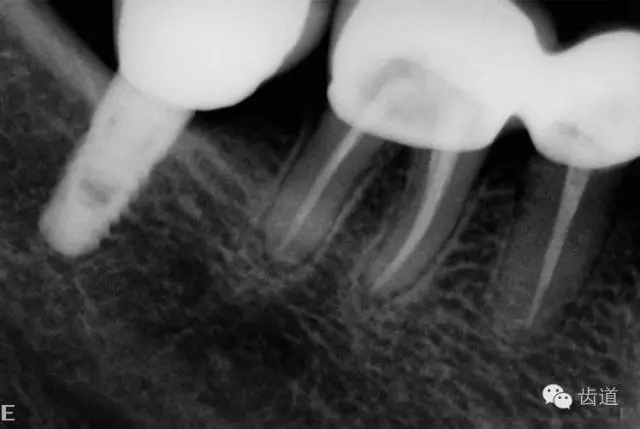

2、45,46術(shù)前片顯示根管上段充填物,根管影像不清晰,少許根尖暗影

45,46去除原充填物和齲壞,揭全髓室頂,46探及近頰近舌遠(yuǎn)中三根管,45單根管,超聲輔助清理髓腔及根管,去除根管內(nèi)充填物,根管下段細(xì)小堵塞欠通暢,8號(hào)/10號(hào)C銼疏通根管,pathfile+protaper鎳鈦根管預(yù)備,熱牙膠根管充填。

5、右下頜側(cè)面觀

6、45,46,47牙片